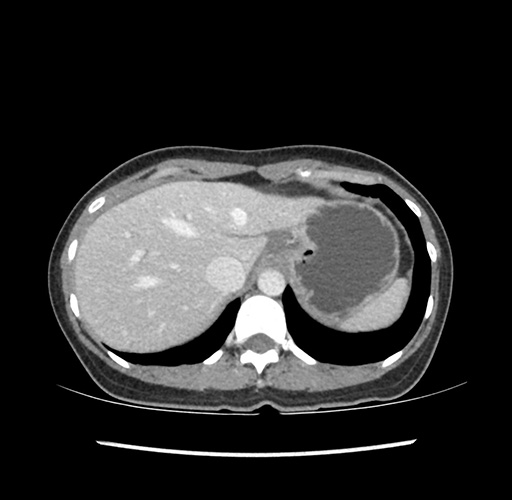

Imaging Analysis

Look through the patient's CT scan to identify any areas of concern for the necessary procedure.

Based on your CT findings, which issue(s) would give reason for "planned slowing down moment(s)" in this case?

Considering a standard left lateral sectionectomy procedure, what step(s) of the operation would you do differently in this case ?